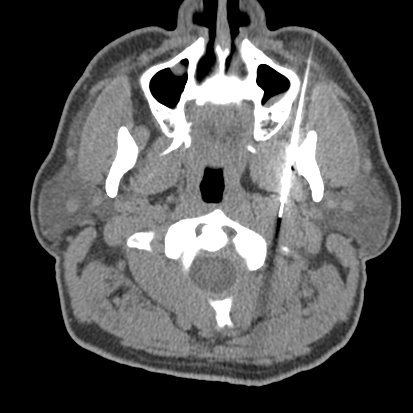

"CT and MRI Findings of Glomangiopericytoma in the Head and Neck: Case Series Study and Systematic Review" |

#HNrad | http://bit.ly/2sPvUYE pic.twitter.com/xjwyidHbAb